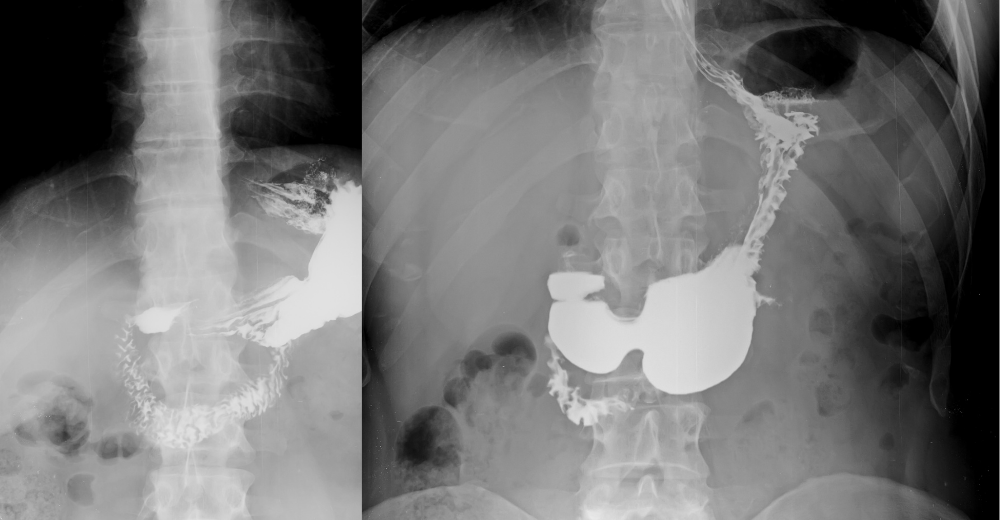

L’Esame RX Esofago con doppio contrasto è una tecnica radiologica avanzata che utilizza un mezzo di contrasto per visualizzare chiaramente le pareti dell’esofago. Questa procedura prevede l’assunzione di una soluzione di contrasto negativo, seguita dall’introduzione di aria, che permette di ottenere un’immagine nitida e dettagliata della superficie interna dell’esofago. Tale metodo è particolarmente utile per identificare lesioni e anomalie che potrebbero non essere visibili con altre tecniche diagnostiche.

Durante l’esecuzione dell’Esame RX Esofago con doppio contrasto, il paziente assume una soluzione di contrasto che aderisce alle pareti dell’esofago, rendendole visibili ai raggi X. Successivamente, viene introdotta aria nell’esofago tramite un sottile tubo, creando un contrasto che permette di osservare con chiarezza le strutture esofagee. Il radiologo acquisisce diverse immagini in varie posizioni del paziente per ottenere una visione completa dell’esofago e individuare eventuali anomalie o patologie.